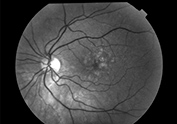

RETINOGRAFIA COLOR (RG)

Nos da información del estado de la retina, nervio óptico y vasos permite controlar la evolución de la misma.